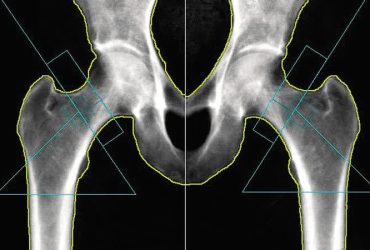

گزارش BMD به روش DXA و نکات مهم در ارزیابی و تحلیل آن

گزارش BMD و نکات مهم در ارزیابی و تحلیل به روش DXA گزارش BMD باید